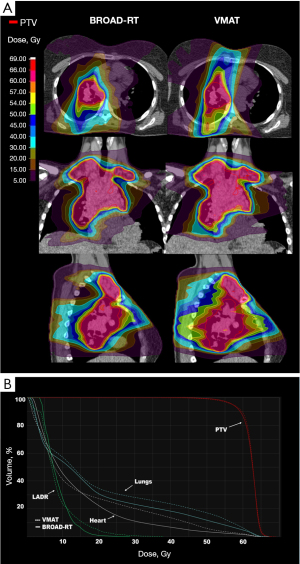

In a case involving two virtual plans, 95% of the PTV delivered 57 Gy because Lungs-V20 <35% could not be met with the 60 Gy prescription. The mean (SD) of PTV-D2 (%), PTV-D50 (%), PTV-HI, and PTV-CI were 110.46 (15.58), 103.06 (0.71), 12.98 (15.10), and 0.90 (0.03) for BROAD-RT and 105.67 (1.86), 103.02 (1.09), 7.87 (4.84), and 0.84 (0.06) for VMAT, respectively. BROAD-RT impacted PTV-CI improvement compared with VMAT (P=0.001; Table 2). However, BROAD-RT did not affect PTV-D2 (%), PTV-D50 (%), and PTV-HI improvement compared to that with VMAT (P=0.35, 0.89, and 0.32, respectively; Table 2). Examples of the BROAD-RT and VMAT dose distributions are presented in Figure 1.

Lung dose-volume parameter comparison between BROAD-RT and VMAT

The mean (SD) of Lungs-V40 (%), Lungs-V30 (%), Lungs-V20 (%), and Lungs-Mean (Gy) was 10.25 (4.99), 14.82 (4.94), 21.64 (5.15), and 13.53 (2.95) for BROAD-RT and 12.41 (5.38), 18.55 (5.11), 26.76 (5.80), and 15.30 (3.32) for VMAT, respectively. BROAD-RT influenced Lungs-V40, Lungs-V30, Lungs-V20, and Lungs-Mean improvement against VMAT (P=0.002, <0.001, 0.001, and 0.001; Table 2). The mean (SD) of Lungs-V5 (%) was 54.67 (9.95) for BROAD-RT and 59.97 (12.40) for VMAT. BROAD-RT did not influence Lungs-V5 improvement compared to that with VMAT (P=0.10; Table 2). Additionally, the mean (SD) of Lungs-V1 (%) was 97.38 (3.98) for BROAD-RT and 90.84 (10.00) for VMAT. BROAD-RT significantly worsened Lungs-V1 outcomes compared to that with VMAT (P=0.01; Table 2).